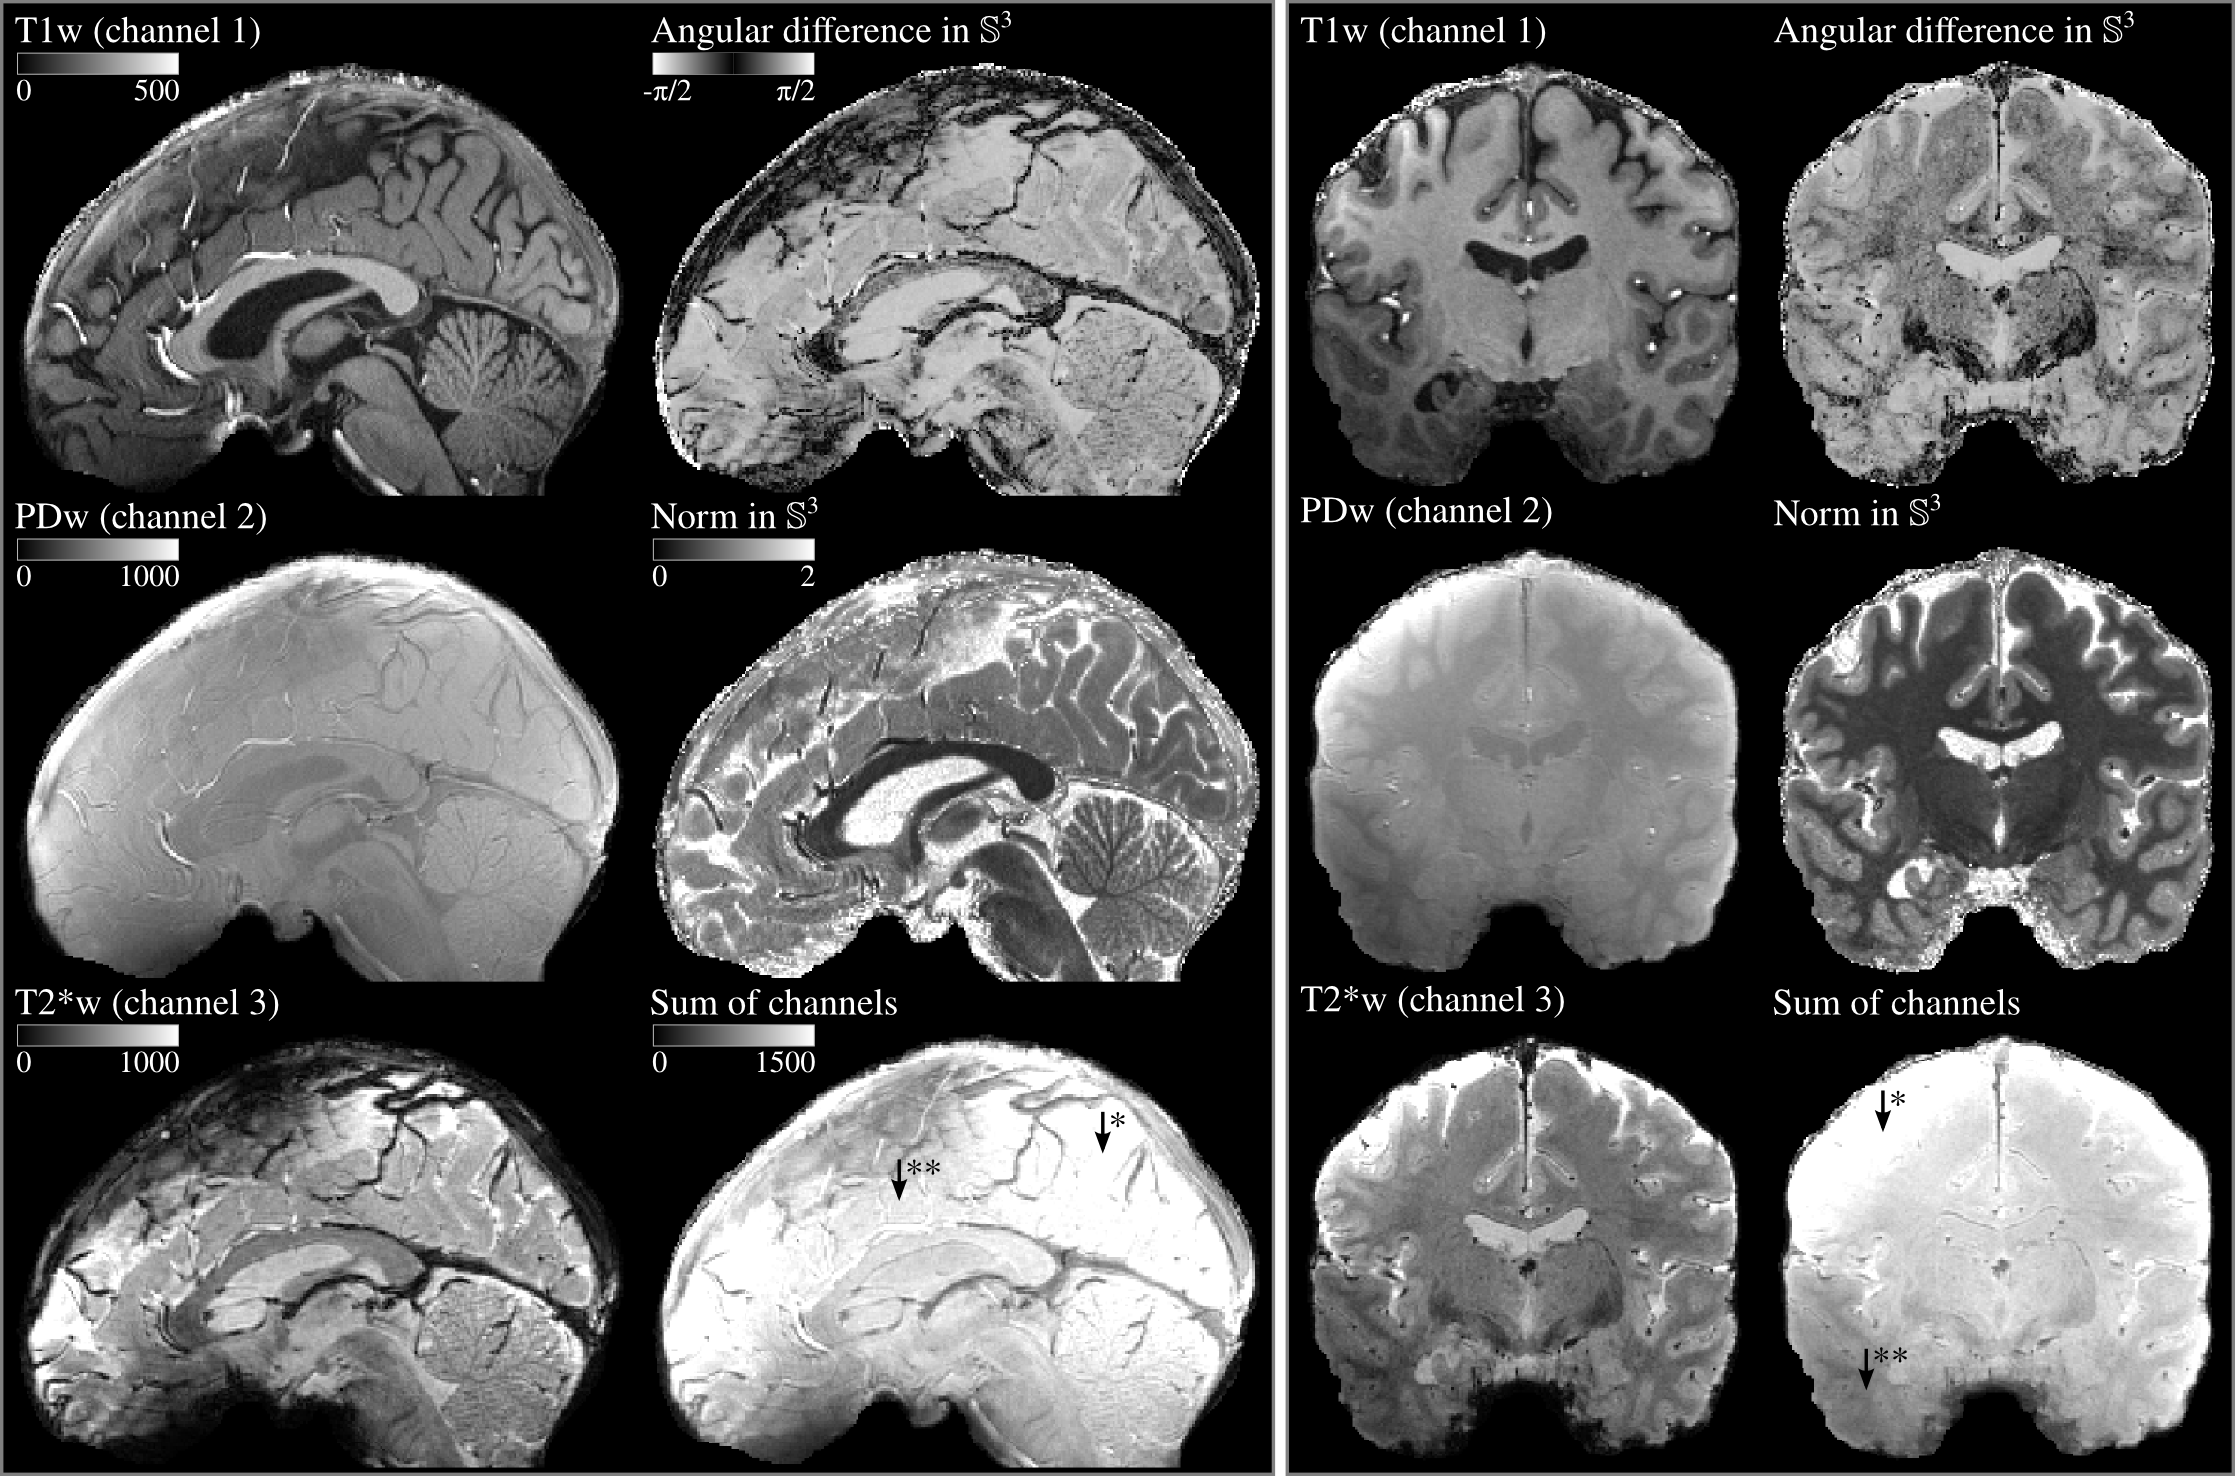

Figure 2: T1w, PDw and T2*w MR images rendered together with angular difference in simplex space ( Eq. 18), norm in simplex space ( Eq. 16) and scalar channel sum component ( Eq. 3). Left panel shows the sagittal slices (y-z plane) and the right panel shows a coronal slices (x-z plane) of the 3D images. Arrows with one asterisk (*) indicates the parts of the images that are too bright and arrows with two asterisks (**) indicates the parts that are too dim as a result of data acquisition imperfections. The legends on the upper left corner in left panel shows the colors bars which are also valid for the images in right panel.

Figure 2 depicts two different slices of the 3D brain images visualized in gray scale depicting different image contrasts. It can be seen that the smooth, artefactual multiplicative scalar field (referred as bias field in MRI literature, see arrows with asterisks in Fig. 2) is separated from the compositional components (compare Fig. 2 rows 1-2 column 2 with row 3 column 2 in both panels). This is similar to the separation of the brightness gradient in the sky in  Fig. 1 as mentioned in the previous paragraph. The compositional image contrasts can be considered as virtual contrasts which enhance the visual appearance by being invariant to certain artefactual features. It should be mentioned that other image contrasts can be generated by changing the reference vector in angular difference images (see Eq. 18) to highlight specific tissues. Similarly, the compositions can also be perturbed (see Eq.8) differently to generate different contrasts in norm images. The generation of task-specific virtual contrasts could potentially be useful in medical imaging applications since the input channels and the virtual contrasts are physically interpretable.